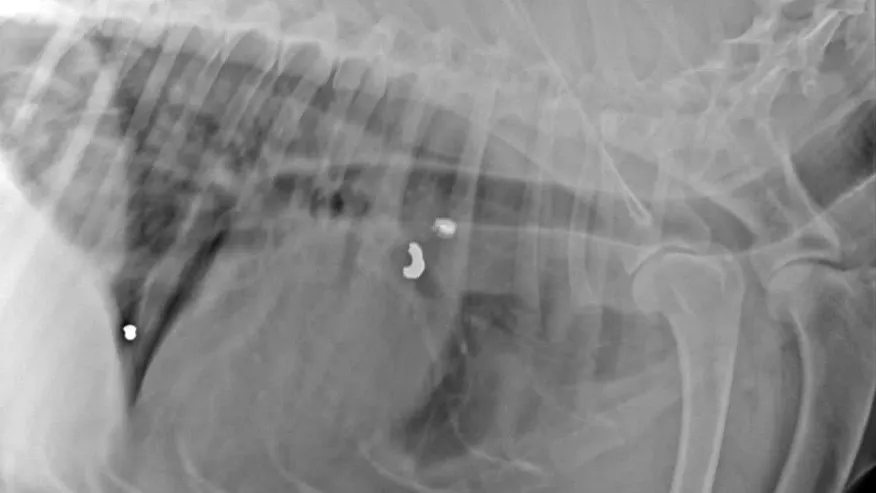

Представители фонда увезли пса в клинику на рентген. На снимках специалисты увидели несколько пуль. Одну из них достать очень сложно, так как она находится около сердца. Собаке необходима операция. Фонд открыл сбор на оплату рентгена и хирургическое вмешательство.

Фото: vk.com/dorogadomoi89